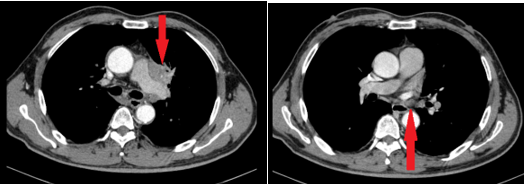

- Chụp cắt lớp vi tính lồng ngực: Hình ảnh khối nhu mô thùy trên phổi trái kích thước 38x38x59 mm, bờ tua gai co kéo gây giãn các nhánh phế quản lân cân, ngấm thuốc mạnh không đều sau tiêm, xâm lấn trung thất. Hạch trung thất dưới carina, dọc quai động mạch chủ và rốn phổi trái, hạch lớn nhất kích thước 14x11 mm.

Hình 3: Hình ảnh cắt lớp vi tính lồng ngực lúc mới chẩn đoán: hình ảnh hạch trung thất cạnh quai động mạch chủ (hình bên trái), hạch rốn phổi trái (hình bên phải).